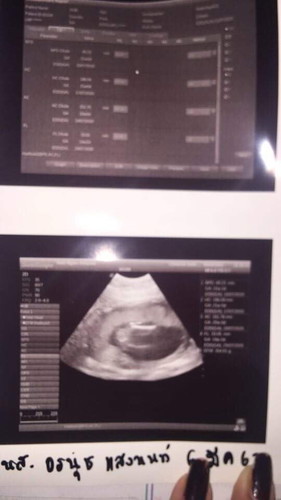

คือท้องได้21วีค 2วัน รุ้สึกแค่อะไรตอดๆนิดๆไม่ถึงกับรู้สึกว่าดิ้น เวลาหมอคำไม่ค่อยเจอบอกหน้าท้องหนา. คือเอาง่ายๆเหมือนไม่ค่อยรู้สึกว่าลูกดิ้นเลยค่ะ เป็นไรไหมคะ แต่ไปหาหมอมาวันที่6 หมอบอกปกติดีค่ะ